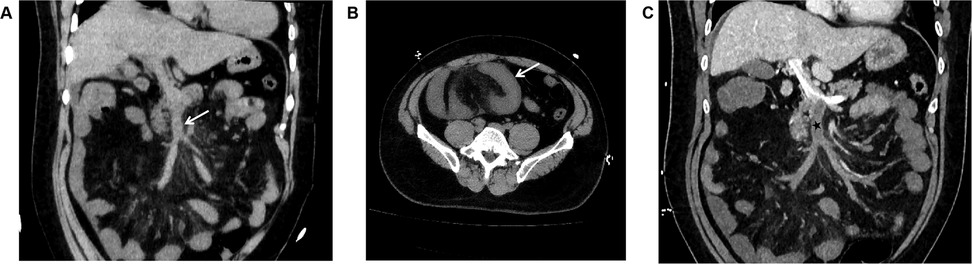

Unenhanced CT scan demonstrated circumferential wall thickening (∼1.05 cm) predominantly involving ileal loops in the right lower abdomen and pelvis. The mucosal surface appeared hyperdense; luminal dilation or high-density intraluminal material was absent. The serosal surface was indistinct, with associated mesenteric swelling, perivascular haziness, and minimal fluid (Figures 2A,B). The SMV and main portal vein trunk were dilated (diameters ∼1.80 cm and ∼2.01 cm, respectively) with increased intraluminal density. Contrast-enhanced CT showed persistent enhancement of the thickened bowel wall mucosa. Filling defects were present within the SMV and main portal vein trunk: the SMV was completely occluded, while the main portal vein trunk showed approximately 50% stenosis; the filling defects showed no enhancement (Figure 2C). Liver parenchymal density and enhancement were unremarkable. A small amount of perihepatic fluid was noted.

Figure 2. (A) In case 2, the non-contrast CT scan in the coronal plane of the abdomen displays enlargement of the superior mesenteric vein, with unevenly increased internal density, blurred vessel wall margins, and swelling of the surrounding mesentery (arrow). (B) In Case 2, The non-contrast CT scan in the axial plane shows thickening and swelling of the ileal wall, with increased density of the mucosal surface, and no dilation of the intestinal lumen. The serosal surface appears blurred, with associated mesenteric swelling, and fluffy shadows surrounding the blood vessels (arrow). (C) In Case 2, The CT scan with contrast during the portal venous phase in the coronal plane demonstrates filling defect changes within the superior mesenteric vein and the main portal vein trunk (black star). The superior mesenteric vein is completely occluded, and the main portal vein trunk is narrowed by approximately 50%, with no enhancement changes observed in the filling defect area. The thickened mucosal surface of the small intestine wall shows persistent enhancement, and a small amount of fluid is present around the liver.